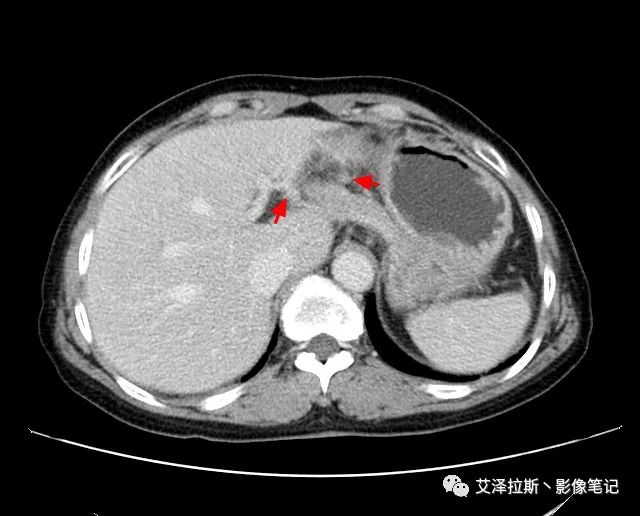

圖1 平掃+增強(qiáng)各期

【影像所見】 胃竇部狹窄,胃壁環(huán)形增厚,小彎側(cè)見一巨大潰瘍,周圍伴“環(huán)堤征”,漿膜面不完整,胃周脂肪見網(wǎng)格狀條索影,病灶與肝臟左葉、胰腺鉤突脂肪間隙消失,增強(qiáng)掃描病灶明顯強(qiáng)化。引流區(qū)內(nèi)約15個區(qū)域淋巴結(jié)受累。

【診斷意見】 胃竇部胃癌(T4N3期) 該病例腫塊突破漿膜層,與肝臟左葉、胰腺鉤突分界不清,脂肪界面消失,定為T4期; 受累及的淋巴結(jié)為15個區(qū)域,定為N3; 有無遠(yuǎn)處轉(zhuǎn)移尚不明確,所以M期暫時無法確定。